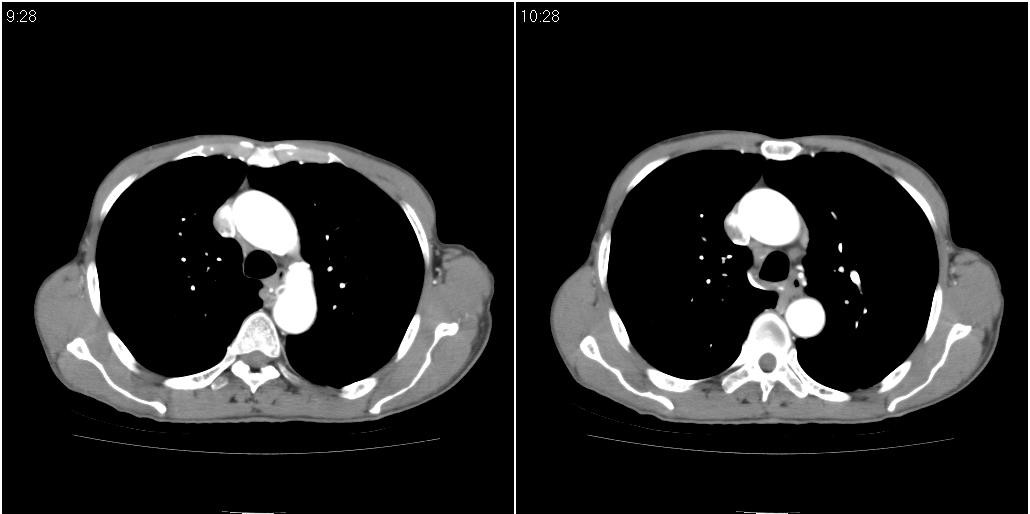

右肺中叶阻塞性不张及肺炎,高度怀疑支气管占位,建议纤支镜检查!

右中肺阻塞性炎症,建议纤支镜!双下支扩感染。

1)右肺中叶慢性炎症并支气管扩张,节段性肺不张。2)两肺下叶支气管扩张。

1)右肺中叶慢性炎症并支气管扩张,节段性肺不张。2)左肺下叶支气管扩张